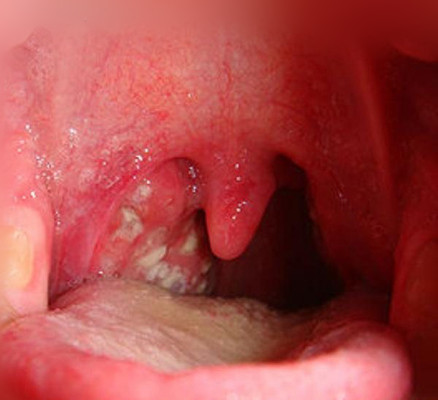

扁桃體週膿腫圖片